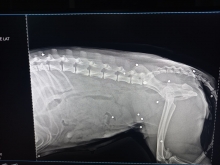

Оренбурженка связалась с волонтёрами приюта "Я - Живой". Удалось найти автомобиль, свозить животное в ветклинику. Как оказалось, её расстреляли из охотничьего ружья. В теле обнаружили 19 дробин. Не было практически ни одного живого места: повреждены голова, лапы, позвоночник, грудь, горло, живот, глаз. Врач отметил, что если бы стреляли с более близкого расстояния, то шансов выжить у бедной собаки не было бы...

Вопрос об операции будет решаться после того, как ее состояние стабилизируется, ей нужно отогреться, так как два дня она пролежала в снегу, проколоть антибиотики, подождать сокращения матки и остановки кровотечения. Одно точно: левый глаз, залитый кровью, видеть не будет, дробь повредила его полностью, - отметили волонтеры.